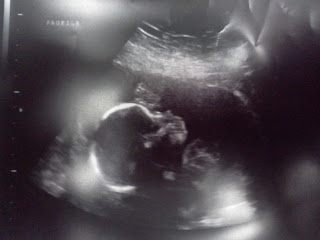

Today I had my "fetal anatomy scan" aka, ultrasound. It was really cool to have the technician pointing out all the parts to us. And lucky she could, cause a lot of it we would not have been able to identify :) It took a little while for us to get a clear shot of "the goods" but we did get one. Soon you all shall know too what we saw :) But here's a sneak peek:

I'm feeling more "tubby" each week. Found another yoga move I can't do this week :) I also felt more pressure on my bladder for a few days. Like use the bathroom and still feel like your bladder is full the minute you leave the restroom. On the ultrasound, it was pretty clear why this was, as the baby was right on top of my bladder. It's weird to think something that's less than 6 inches long and only weighs 11 ounces can make such an impression. It's also weird to see all the movement on the ultrasound but not be able to feel it at all yourself.

So, here I am right before the ultrasound this week. And baby's weight is approximately the 50th percentile, so we are right on track for growth.